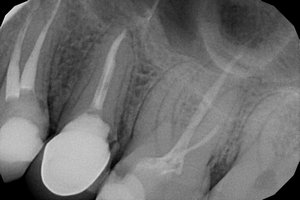

В середине ноября у меня разболелся зуб - верхняя правая 5-ка. Боль тупая, ноющая, иногда с ощущением распирания. Поставили диагноз пульпит, удалили нерв. Но после лечения оставалась легкая боль при накусывании, в январе зуб начал также реагировать на перкуссию. Я посетила консультацию у другого врача, сделала рентген. Мне сказали, что зуб запломбирован нормально, это может быть просто реакция организма на переохлаждение. Со времени той консультации прошел месяц, боль не ушла, зуб стал реагировать на горячее ощущением распирания. Еще иногда я замечаю неприятный привкус, идущий из пространства между этой 5-кой и 6-ой, как будто там что-то гниет.

Что за проблема это может быть? Нужно ли перелечивать зуб? И с какими рисками может быть связано перелечивание?

На мой взгляд, зуб пролечен хорошо, но для полной картины и оценки необходим К/Т (трехмерный снимок). Все симптомы говорят о периодонтите.